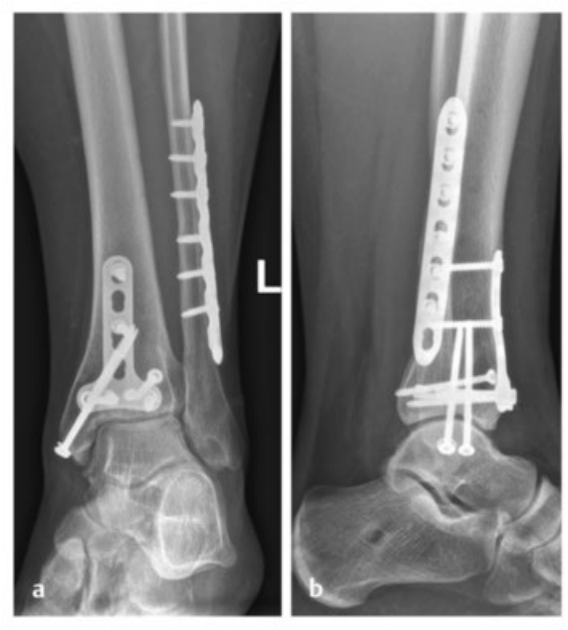

病例1在受伤后送往医院急诊,首先进行了跨踝关节外固定架。尽管患者初始存在Ⅱ度闭合性软组织损伤,但由于及时进行了复位并植入外固定架,未需实施筋膜间室切开术。在术前CT图像中,可清晰观察到3个主要骨折块及1个中央粉碎区。通过及时植入外固定架,可恢复关节位置,并有效避免软组织损伤进一步加重。

待软组织状况改善(出现 “皮肤皱纹征”)后,开始对患者进行手术治疗,首先处理腓骨(遵循 “先处理腓骨” 原则)。术中检查发现韧带联合存在不稳定情况。

术中三维CT 扫描确认骨折达到解剖复位,内植物位置良好。术后影像学检查证实骨折解剖复位,内植物位置正常。患者术后恢复过程顺利,关节功能恢复良好。